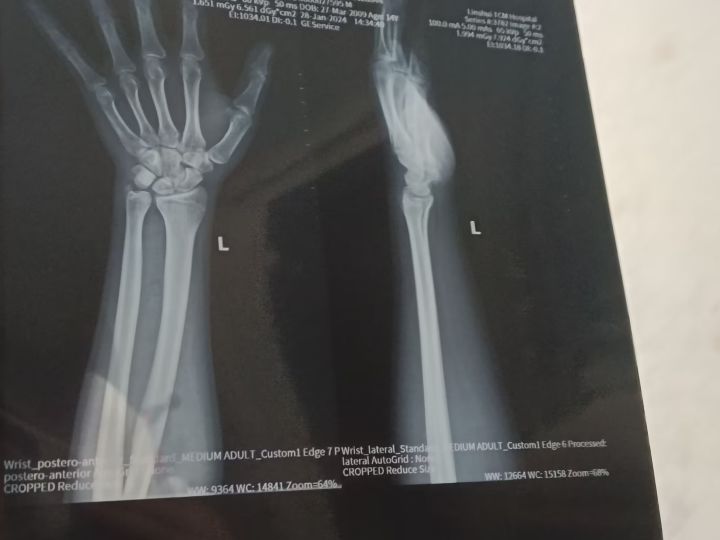

最近手旋转提东西的时候有点痛,然后去医院检查了一下,照了片,结果是先天性尺骨撞击,这个就是骨头长的太长了,影响到其他骨头的运动和移动,医生说这个没有办法,只有看以后这个尺骨会不会再继续长

简单明了地说,就是要把这个长的那一段锯掉,也就是做手术,但是手术有极大后遗症,可能导致手腕不能大幅度旋转什么的,反正阿巴阿巴不好的地方